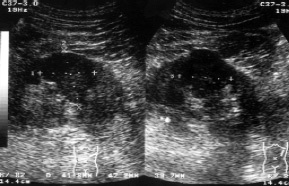

A vizsgálat a regionális nyirokmasszázs területeken a pajzsmirigy - okolotrahealnyh, mély nyaki (cervicalis), állkapocs alatti és kulcscsont feletti - kóros elváltozásokat csak a jobb kulcscsont feletti régióban. A jobb supraclavicularis zóna echografically különbséget három hypoechoic szilárd anyag képződésének 15,6x17,1, 21,7 mm-es és 29,4x24,1, amelyek közül az utolsó - tapintható (2. ábra).

Ábra. 2. Metastaticheskoie vereség szupraklavikuláris nyirokcsomók.